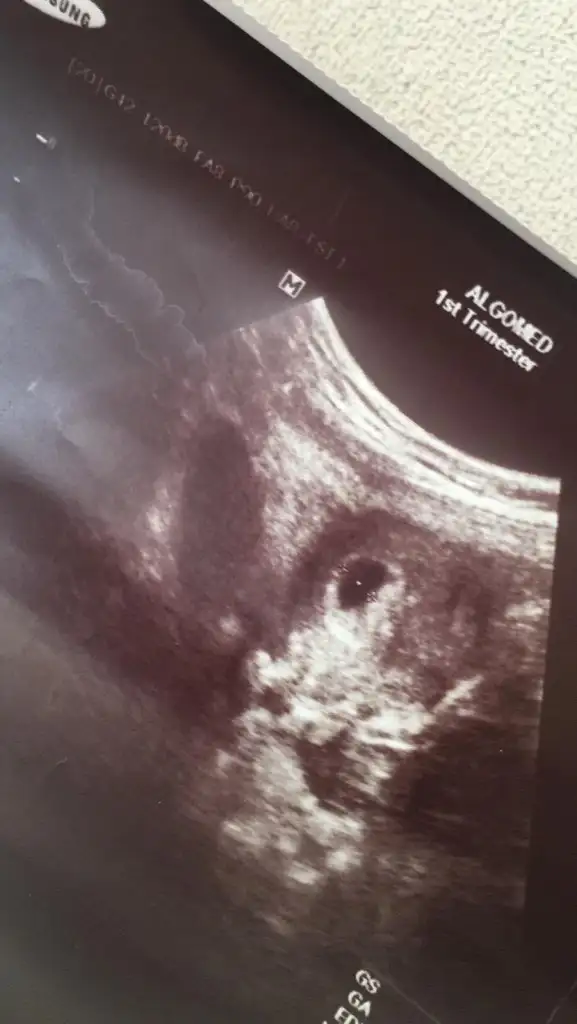

Ay ne kadar tatlış maşallah nasılda durmuş tüm resimlere baktım da bu dikkatimi çekti çok güzel durmuş minnacık Allah hayırlısıyla kucağına almayı nasip etsinMeraba arkadaslar benimki içinde tahminde bulunursaniz çok sevinirim 10 haftalik![]()

Haftaniza göre bebek gelismis baya erkek çocukları daha çabuk gelişir derlerNerden anladiniz acaba? Bizimde isteğimiz önce sağlıklı hayırlı evlat sonra erkek olması Rabbim gönlümüze göre versin inşallah.